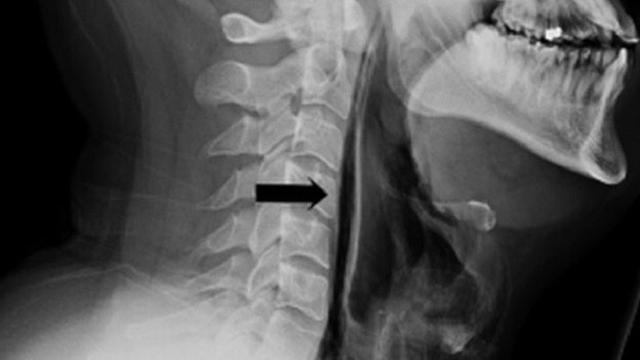

Peristiwa tersebut, yang dilaporkan dalam jurnal medis BMJ Case Reports pada 2018, menyebutkan bahwa pasien yang tidak disebutkan namanya berusaha untuk menghentikan bersin dengan "menjepit hidung dan menutup mulut."

Tak lama kemudian, tenggorokannya sakit ketika dia menelan dan ada "perubahan suara". Terlebih lagi, lehernya bengkak dan ketika dia memindahkannya, ada sensasi letupan dan retakan yang meresahkan.

Ternyata, pasien mengalami emfisema subkutan dan pneumomediastinum. Sinar-X yang diambil menunjukkan bahwa udara yang seharusnya meledak dari hidung dan mulutnya masuk ke jaringan lunak lehernya.

Pria itu pulih dalam seminggu atau lebih, dan terus membaik setelah dua bulan pemulihan. Tetapi bisakah itu terjadi pada orang lain? "Ini jarang terjadi dalam konteks jumlah bersin yang terjadi setiap hari di seluruh dunia," kata Dr Stephen Lee, seorang konsultan dan ahli bedah Telinga, Hidung dan Tenggorokan (THT) dengan Rumah Sakit Raffles.